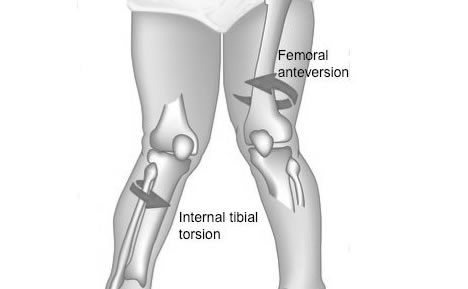

Torsión de Tibias

Esta afección se refiere a la torsión hacia adentro de los huesos que están entre la rodilla y el tobillo. Hace que los pies del niño apunten hacia adentro. Se percibe comúnmente en niños que empiezan a caminar. Puede ser ocasionada por la posición del bebé en el útero.